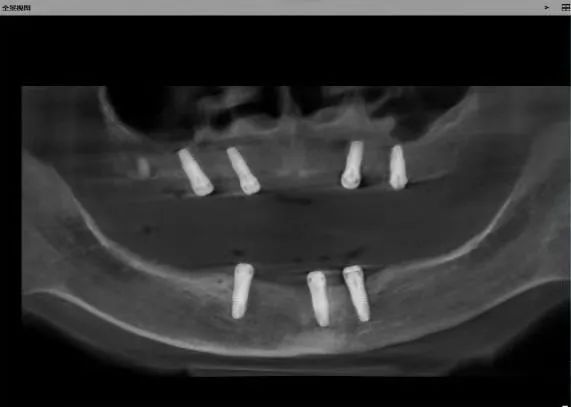

今年5月,患者常女士,全口牙齿缺失十余年,因咀嚼功能较差长期苦恼而求诊,靳勇结合患者病情,设计个性化种植导板,做足术前准备,目前已顺利完成全口无牙颌种植体植入术,待后期牙齿修复。

个性化种植导板

种植体植入术后